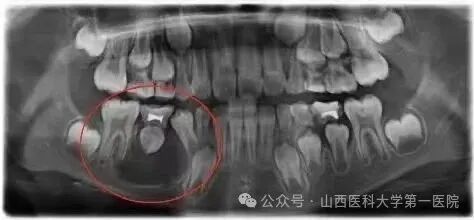

全景片(曲面断层片):最常用、最经济有效的筛查手段,可以一览全口牙齿和颌骨情况,就像给颌骨拍了一张“集体照”,囊肿无处遁形。

悄无声息,早期毫无症状,这是它最“狡猾”的地方。在囊肿生长的初期和中期,患者往往没有任何感觉,不痛不痒,很多人是在例行口腔拍X光片时才被意外发现。

暗中扩张,疯狂“挖空”颌骨,囊肿会持续性地、缓慢地膨胀,像蚂蚁啃堤一样,一点点“吃掉”周围的骨质。最终,颌骨会被侵蚀得只剩下一个空壳,骨质变得像蛋壳一样薄,大大增加了病理性骨折的风险。

伤及无辜,波及健康牙齿,巨大的囊肿会挤压邻牙牙根,导致牙齿松动、移位,甚至牙根被吸收,最终让好牙也无辜“殉职”。